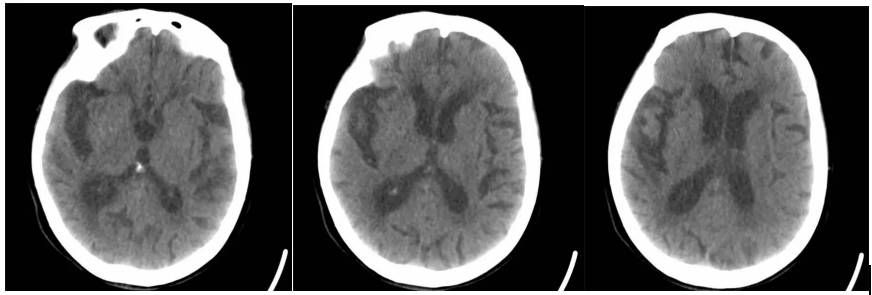

脑科手术室脑损伤移动CT床旁脑部扫描